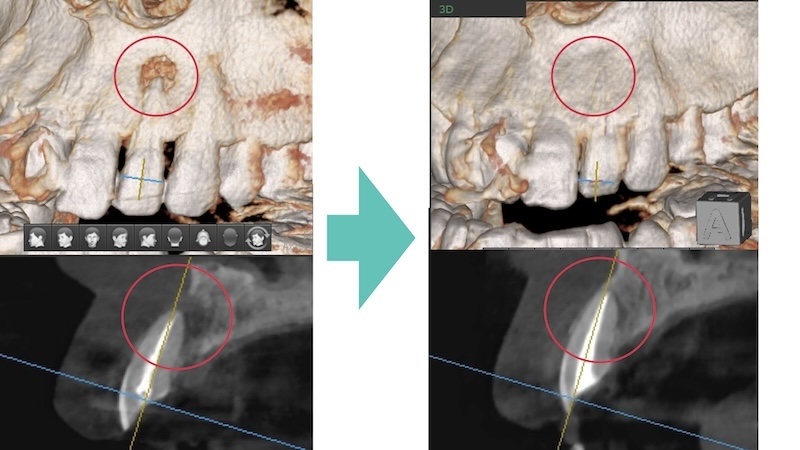

半年後の結果|「抜歯」から「自分の歯で噛める」へ

半年後、歯科用CTで確認したところ――

👉 骨の欠損がほぼ完全に回復

どこに病変があったのか分からないほど、きれいに治癒していました。

骨がしっかり再生

治療前後で骨の状態が大きく改善

※治療前後の比較(同一症例)